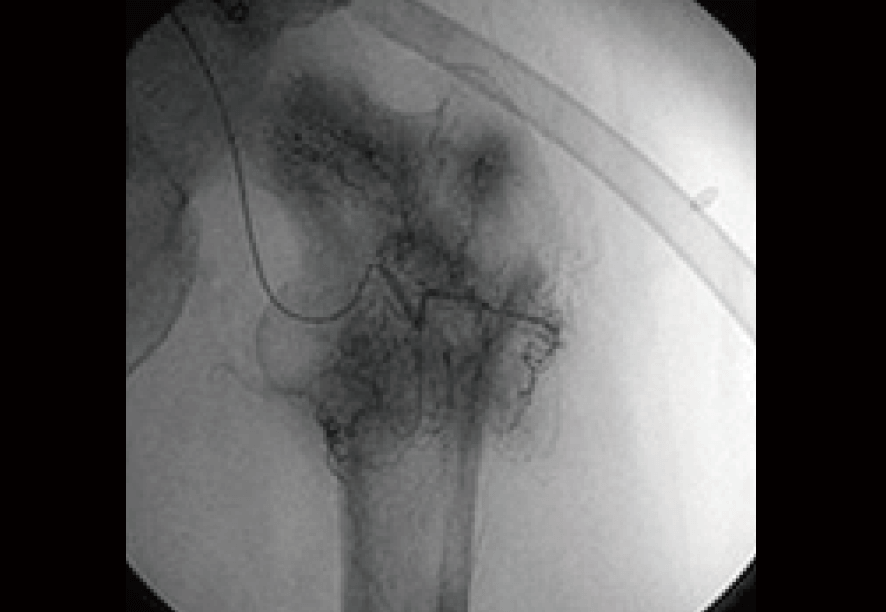

免疫治療前に血管カテーテルによって転移したがんそのものを調査した時の画像。

大たい骨の周囲にもやもやとしたがんの新生血管が 密に認められる。(黒い部分)

当然この状況まで進んでしまうといわゆる保険治療で実施される標準治療での根治見込みは全く無い。

いわば“治療の手立てなし”という状況である。この時点の予後見込みはおよそ3ヶ月から半年程度。